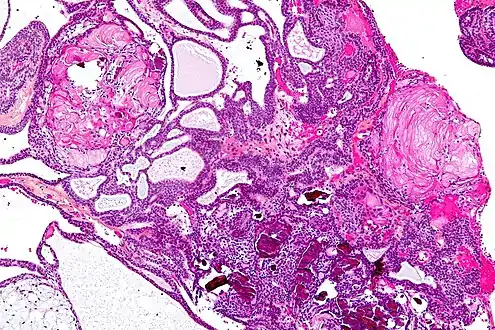

In some cases, a powerful 3T (Tesla) MRI scanner can help define the location of critical brain structures affected by the tumor. The histologic pattern consists of nesting of squamous epithelium bordered by radially arranged cells. It is frequently accompanied by calcium deposition and may have a microscopic papillary architecture. A computed tomography (CT) scan is also a good diagnostic tool, as it detects calcification in the tumor.[21]

• Adamantinomatous craniopharyngiomas, which resemble ameloblastomas (the most common type of odontogenic tumor), are characterized by activating CTNNB1 mutations.

In the adamantinomatous type, calcifications are visible on neuroimaging and are helpful in diagnosis.

On macroscopic examination, craniopharyngiomas are cystic or partially cystic with solid areas. On light microscopy, the cysts are seen to be lined by stratified squamous epithelium. Keratin pearls may also be seen. The cysts are usually filled with a yellow, viscous fluid rich in cholesterol crystals. Of a long list of possible symptoms, the most common presentations include headaches, growth failure, and bitemporal hemianopsia.